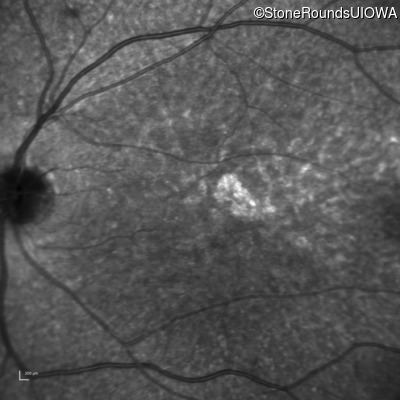

Age at visit: 30 years

This 30 year old man first noticed poor vision in dim light when he was five years old. His visual acuity began to fall in his early 20's.

Macular Disease WDR19 His344Arg CAT>CGT Ser485Ile AGT>ATT AR